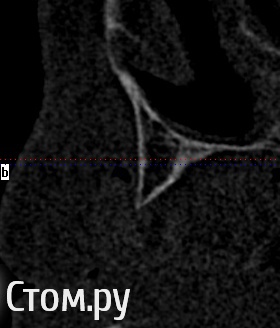

Mane Опубликовано 19 января, 2014 Поделиться Опубликовано 19 января, 2014 репозиция нерва. установка имплантатов. далее нерв укладываете латерально. посмотреть бы еще несколько срезов от 36 до 46 Ссылка на комментарий

АнтонТЛТ Опубликовано 19 января, 2014 Поделиться Опубликовано 19 января, 2014 (изменено) Дистально ветвь нижней челюсти, а не пики альвеолярного отростка. На такую высоту за один раз не поднять (если делать 3д) Изменено 19 января, 2014 пользователем АнтонТЛТ Ссылка на комментарий